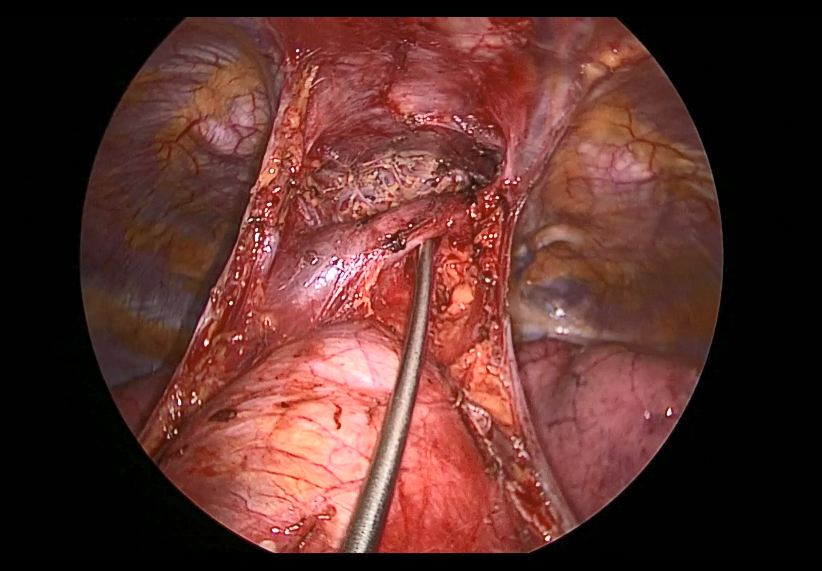

Pictured: Subxiphoid Uniportal Nonintubated Thymectomy

Joel Dunning, Enoch Akowuah, Emily Farkas - Subxiphoid Uniportal Nonintubated Thymectomy

Guseppe Aresu, Giacomo Argento - Adult Supravalvular Aortic Stenosis: Modified Three-Patch Aortic Root Reconstruction